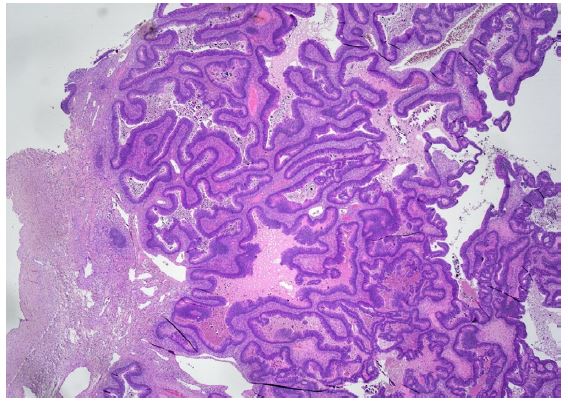

An abdominal Computed Tomography (CT) scan discovered a dilated colon up to the splenic flexure. A CT scan did not show regional nor distant metastases. Subsequently, the patient underwent exploratory laparotomy, which showed an obstructive tumour in the middle of the transverse colon, and there were no signs of macroscopic metastases in the abdominal cavity. The patient underwent resection of the transverse colon with end-to-end anastomosis. Postoperatively, the patient recovered well. Histopathological examination of the specimen revealed a moderately differentiated tubar adenocarcinoma, irregularly infiltrating the serosa, without lymphovascular invasion (Figure 1a), (T4a) and without nodal involvement (11 negative pericolic and 1 negative mesenteric lymph nodes were found); pT4a, N0, M0 (stage IIA); R0 resection was performed. Microsatellite instability-high (MSI-H) cancer was not proven.

Nevertheless, the patient was assessed by a colorectal Multidisciplinary Team (MDT) at Masaryk Memorial Cancer Institute (MMCI), which decided on adjuvant therapy for the stenotic tumour. Adjuvant chemotherapy on the base of 5 fluorouracil (FU/FA Mayo) was administered. However, this was converted to monotherapy capecitabine due to an allergic skin reaction and neutropenia grade IV. Further therapy was uncomplicated, and close follow-up was recommended. An elevation of tumour marker Carcinoembryonic Antigen (CEA) of 21,8 μg/l was found in October 2017. However, a normal level of the Carbohydrate Antigen (CA) 19-9 of 25.2 ng/ml was noted. Subsequent assessment revealed a left ovarian mass with suspicion of a metastatic process. In November 2017, the patient underwent a gynaecologic evaluation followed by explorative laparotomy at the Department of Gynaecology in the University Hospital Brno. A hysterectomy with bilateral oophorectomy and appendectomy was performed, and malignant ascites was also found. Histological findings showed metastases of moderately differentiated intestinal adenocarcinoma in the left ovary (Figure 1b), identical to the primary transverse colon tumour resected in 2013. KRAS, NRAS and BRAF gene mutations were not detected. The postoperative recovery was uncomplicated, and the patient was referred back to medical oncologists at MMCI. A follow-up Positron Emission Tomography/Computed Tomography (PET/CT) scan was performed in December 2017. It discovered a small metabolically active lesion measuring 12 mm located in the pyloric region closer to the gastric, small curvature (Figure 2). Tumour marker CEA was again slightly elevated (9,4 μg/l) (Figure 3). A gastroduodenoscopy showed prominent gastric walls in the region of the angular notch without mucosal changes. A biopsy was taken, and histologic examination revealed benign atrophic gastritis only (Figure 4).

However, based on the results of PET/CT, tumour marker elevation, malignant ascites, previous results and the course of the disease, the case was discussed at the colorectal MDT in the MMCI. The MDT recommended explorative laparotomy. In February 2018, surgery was performed with findings of a gastric lesion and multiple peritoneal metastases. Gastric resection in Billroth I modification with small and great curvature lymphadenectomy and omentectomy was performed, followed by cytoreductive surgery, resection of the peritoneum, and HIPEC for 90 minutes with cisplatin and mitomycin using Rand’s Performer HT device (Medolla, Italy). The postoperative recovery was uncomplicated, and the patient was discharged on the eleventh postoperative day. Histologic examination found metastases of moderately differentiated adenocarcinoma of colorectal origin with perineural invasion in the gastric antrum wall without mucosal changes (Figure 1c). Six lymphatic perigastric and five omental lymph nodes were harvested, and all nodes and peritoneal strips were negative for cancer. Adjuvant chemotherapy based on capecitabine and oxaliplatin (XELOX) was administered and the patient was followed in four-month intervals.

Figure 1a: Microscopic histological findings. A resected specimen of the sigmoid colon showed an irregular ulcerated lesion. A histological examination of the resected specimen of the sigmoid colon revealed a moderately differentiated adenocarcinoma invading the subserosal layer. (×100 magnification; haematoxylin and eosin stain).

Figure 1b: Microscopic histological findings. A resected specimen of the sigmoid colon showed an irregular ulcerated lesion. A histological examination of the resected specimen of the sigmoid colon revealed a moderately differentiated adenocarcinoma invading the subserosal layer. (×100 magnification; haematoxylin and eosin stain).

Figure 1c: Microscopic histological findings. A resected gastric specimen showed a moderately differentiated intestinal adenocarcinoma without mucosal changes. A low- and high-power microscopic view of the mass in the stomach revealed moderately differentiated adenocarcinoma (×100 magnification; haematoxylin and eosin stain).

Figure 1d: Microscopic histological findings. A resected specimen of the abdominal wall showed a moderately differentiated intestinal adenocarcinoma (×100 magnification; haematoxylin and eosin stain).